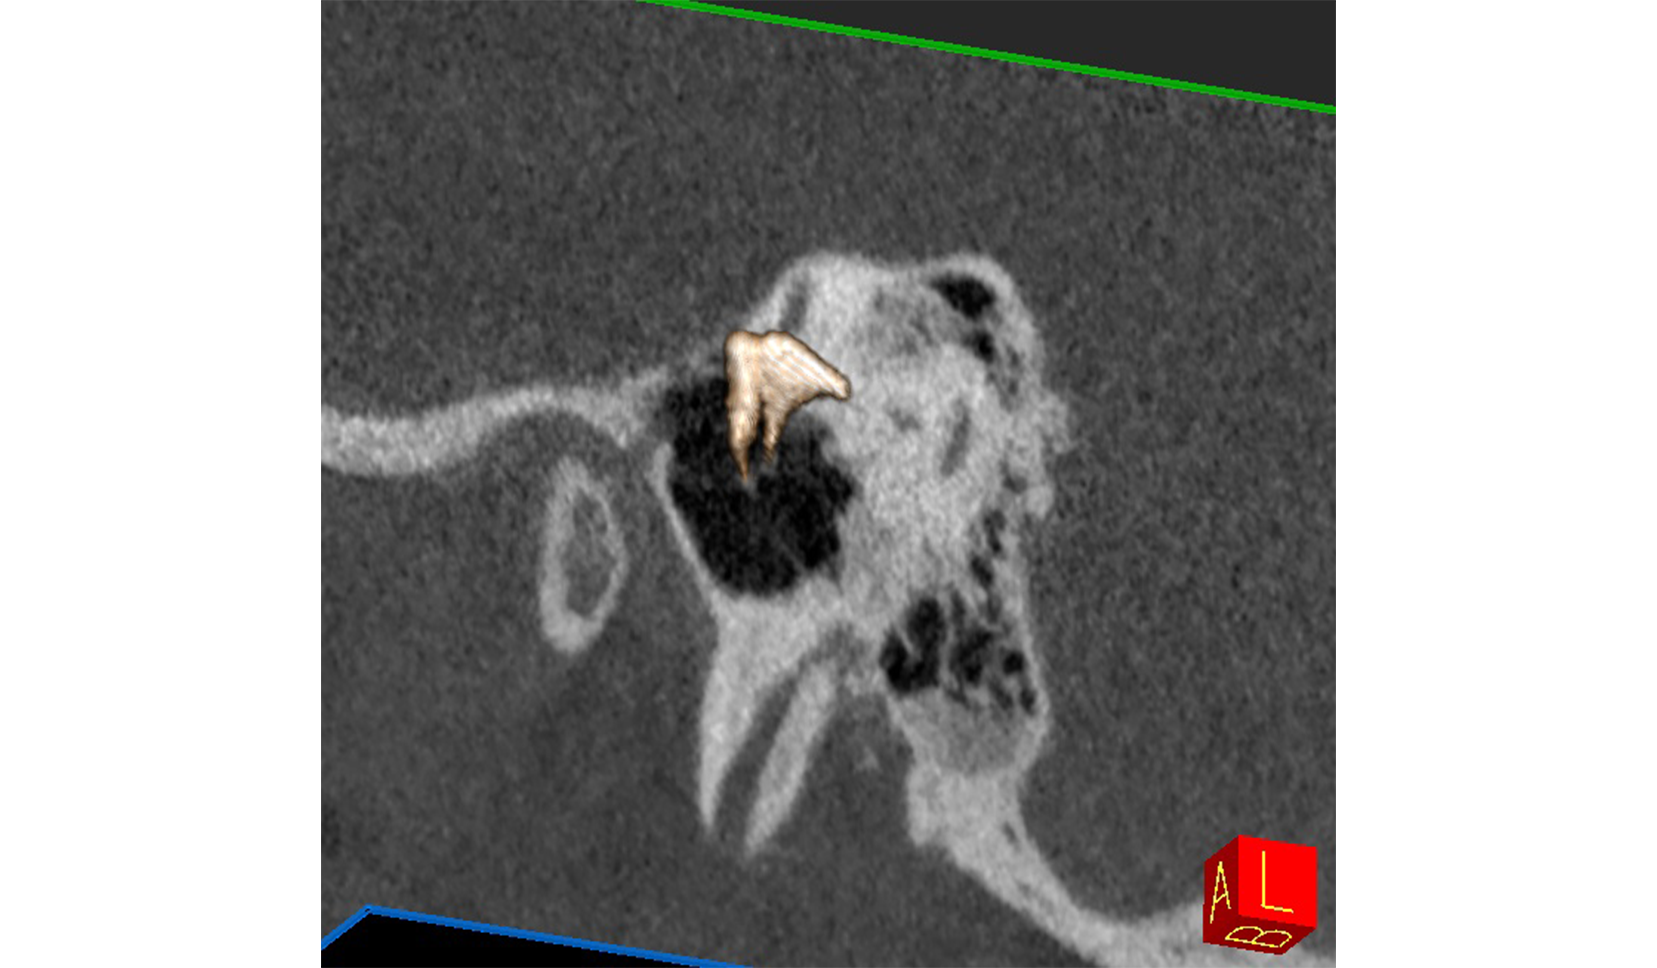

Articulación Témporo Mandibular (ATM)

Cadena Osicular DER IZQ